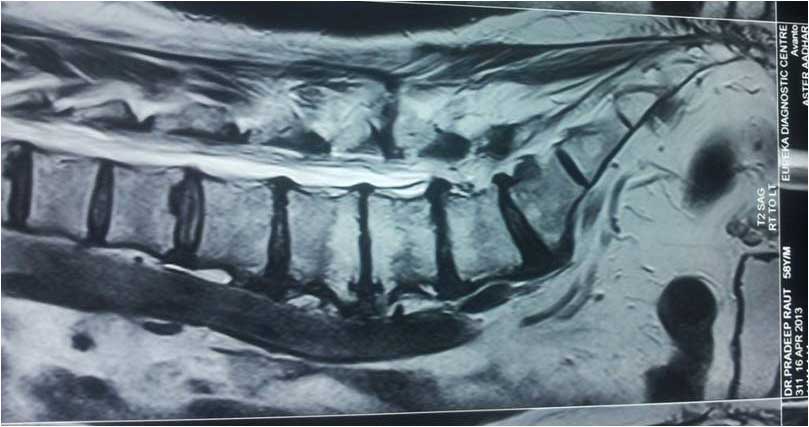

lumbar disc confusing with tumor